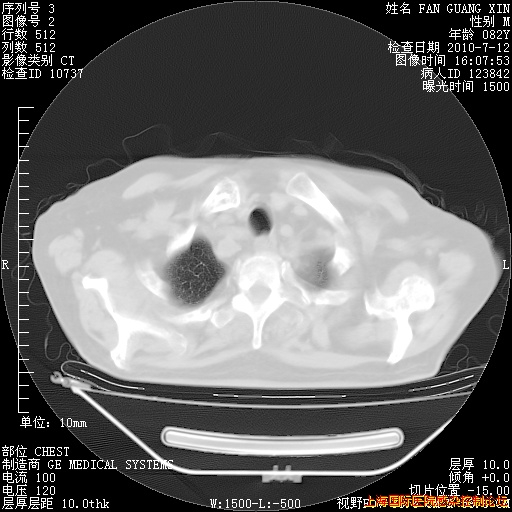

补发6月12日肺部CT肺窗

6月12日肺窗

6月12日纵膈窗

整整相隔30天的肺部CT好像有所好转啊。甲强龙减量第3天,需要观察体温。